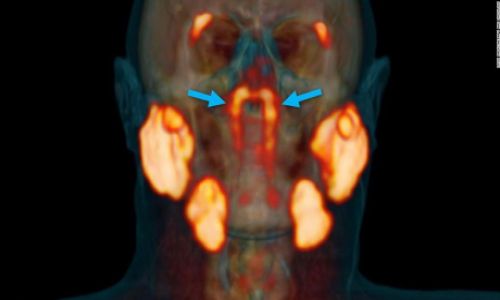

Este conjunto de glándulas salivares se encuentra escondido en nuestra cabeza y fue descubierta por pura casualidad, cuando se le realizaban pruebas a diferentes pacientes con un escáner avanzado llamado PSMA PET / CT. Y es que, combinado con inyecciones de glucosa radiactiva, que sirva para que se resalten los tumores en el cuerpo al realizar las pruebas, mostró estas glándulas en la parte posterior de la nasofaringe.

Este descubrimiento podría tratarse del cuarto conjunto de glándulas salivares que tenemos en nuestra cabeza. Están ubicadas detrás de la nariz y sobre el paladar, más o menos en el centro de nuestras cabezas. Matthijs Valstar, primer autor del estudio, de la Universidad de Amsterdam declara “las dos nuevas áreas que se iluminaron resultaron tener otras características de las glándulas salivales también. Las llamamos glándulas tubarias, refiriéndonos a su ubicación anatómica”.